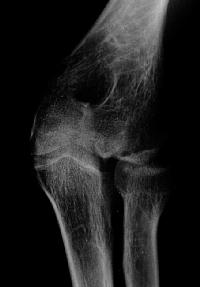

Plain films show humeral osteophytes and posttraumatic changes of the capitellum and radial head.